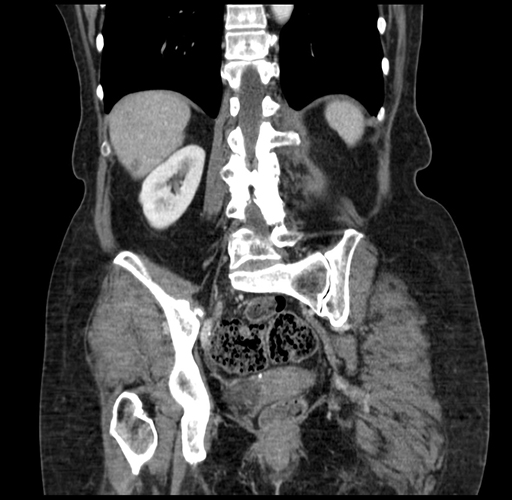

Axial Venous